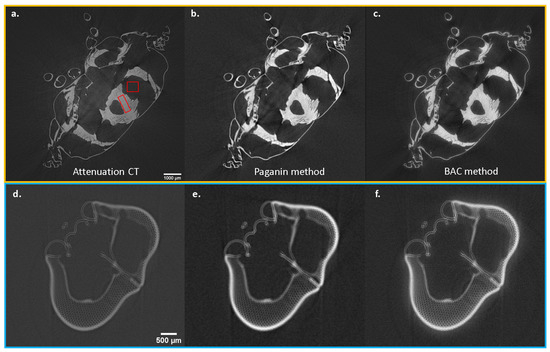

3.3. Example for Grating-Based PCI